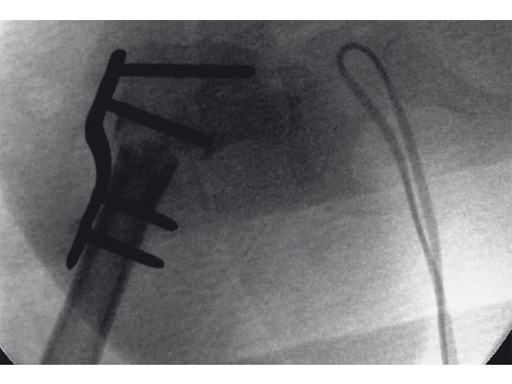

An 18-month old girl presented with developmental dysplasia of the hip. She had failed conservative management with a Pavlik harness, and redislocated following open reduction and femoral osteotomy of the right hip. She underwent revision open reduction and femoral osteotomy of the right hip, followed by the same procedure on the left hip 6 weeks later.

Case provided by James B Hunter, Nottingham, UK